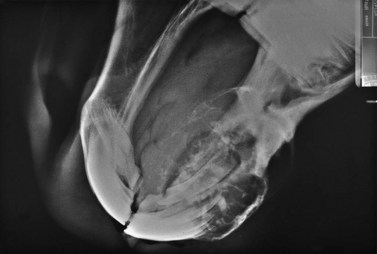

With both wire loops extending out of the oral cavity, the foal is placed in dorsal recumbency with a pad placed caudal to the poll to hyperextend the neck so that the roof of the mouth lies parallel to the ground. The loop wire around the first two cheek teeth is pulled tight and twisted several times on itself in the interdental space. Including the occlusal surface of the upper 2nd premolar in the twists is avoided by keeping the wire close to the hard palate and pulling downward on the buccal wire and upward on the palatal wire while twisting. The twisted strands from both sides are pulled rostrally and brought around the labial edge of the upper incisor arcade and twisted together. The wires should lie across the labial surface of the incisors at the gingival margin. The ends of the wires are cut and tucked between two incisors. An image-inch-thick plate of aluminum with several 3.5 mm perforations is sized so that it fits over the occlusal surface of the upper incisors and extends caudally over the hard palate image inch caudal to the point at which the lower incisors contact the hard palate (Fig. 19.11A). Paraffin rope is placed around the gingival margin of the upper incisors, pulled under the wires on each side, and extended several centimeters caudally on the hard palate to form a dental dam to contain the unset acrylic (Fig. 19.11B). Hard-setting dental acrylic is mixed and formed into the roof of the mouth, within the confines of the paraffin rope, incorporating the wires and labial surface of the upper incisors. The acrylic should cover the knot in the wire on the labial aspect of the upper incisors to prevent the knot from irritating soft tissue. Splinting of the upper incisor arcade with acrylic stabilizes the teeth and prevents the force of the orthodontic wires from spreading or twisting the incisors. The acrylic band wrapping around the labial surface of the upper incisors and the orthodontic wires hold the acrylic firmly in the roof of the mouth. The acrylic is formed with the curved, rostral edge of the metal plate resting on the occlusal surface of the upper incisors and the caudal, straight edge of the plate level or slightly more ventral in the mouth than its rostral edge. This creates a flat or inclined surface for the lower incisors to contact (Fig. 19.11C). This inclined plate frees the mandible from caudal force imposed on it by the upper incisors and creates a slight rostral pull on the mandible as the lower incisors slide over the plate during chewing. As the foal chews, upward pressure is applied to the upper incisors and premaxillae, forcing them into a more normal position (Fig.19.12).

image

Fig. 19.11 (A) Parrot-mouthed foal placed in dorsal recumbency with orthodontic retention wires in place. An aluminum plate is cut and sized to fit the occlusal surface of the upper incisors while projecting caudally to contact the occlusal surface of the lower incisor arcade. A dam of paraffin rope has been built to retain the acrylic mouth piece. (B) Acrylic and thin plate in place. (C) Lateral view showing final placement of wires and acrylic mouth piece.

Fig. 19.12 (A) Lateral radiograph of the rostral skull of a 4-month-old foal with an overjet and overbite just prior to surgery (B) Lateral skull radiograph of foal with orthodontic retention wires placed behind the upper third premolar and encircling the upper incisor arcade. The metal incline plate has not been sloped for this first application of retention wires because creating a slope would have caused a gap in the premolar arcades. The second appliance will have a slope or mechanical incline to encourage rostral growth of the mandible.